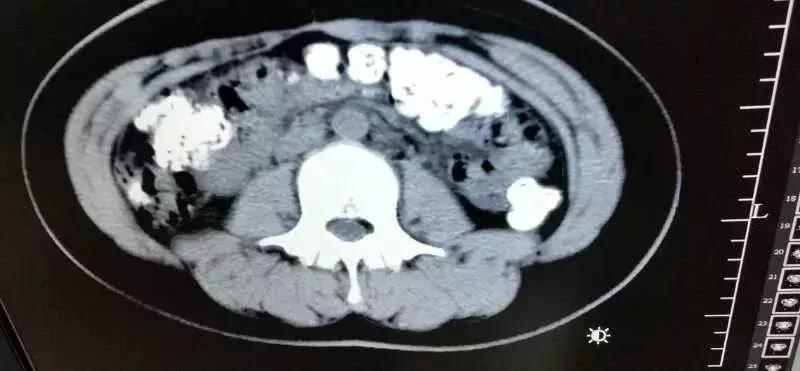

急诊科医生张楼炜对朱丽进行了初步检查,发现她肚子鼓鼓的,就让她去做了腹部CT,谁知道,拍出来的片子让张楼炜大吃一惊,患者胃部、横结肠、升结肠、降结肠、乙状结肠,一直到肛门,全是颗粒状阴影,足有百余颗。

14岁女孩喝了珍珠奶茶后,五天没有排便,还肚子疼,CT检查发现胃肠道,布满一颗颗圆圆的高密度阴影,肠胃道里全是“珍珠”